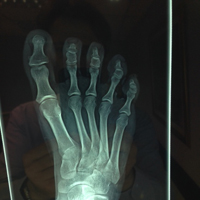

• Επώδυνη παραμόρφωση πέμπτου δακτύλου

Επεμβάσεις μαλακών μορίων